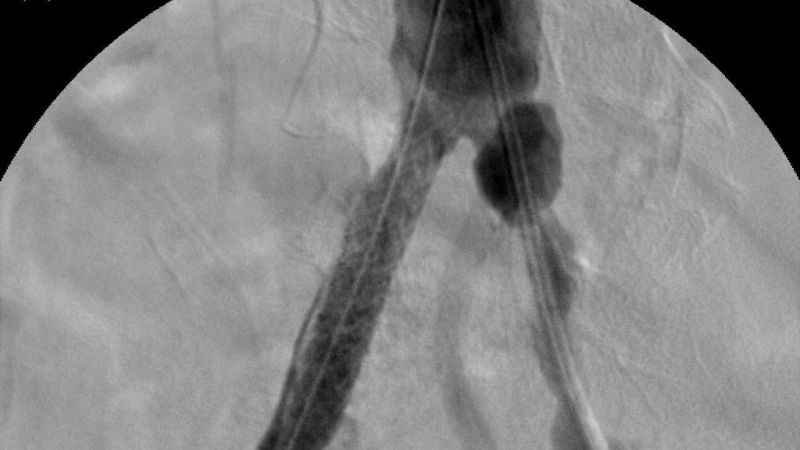

Özellikle anjiyografik yöntemlerle ameliyat gerektirmeden tedavi olanağı sunuluyor. Balon, stent ve damar tıraşlama yöntemleri, bu tedavilerin başında geliyor. Bu tedavilerde kullanılan tıbbi cihazların üretimi bir zamanlar yalnızca belirli ülkeler tarafından yapılırken, artık Türkiye kendi cihazlarını üreterek dünya sahnesinde yer alıyor. Bu alanda yaşanan en büyük yeniliklerden biri de "stent greft" teknolojisi oldu. Üretimi dünyada sadece 5 ülke tarafından yapılan stent greft üretimi ile Türkiye, tıbbi inovasyon alanında tarihi bir başarıya imza attı. Bu büyük adım Türkiye'nin sağlık teknolojilerindeki gelişimini küresel arenada da tescilledi.

Türkiye'nin ilk yerli stent grefti Bezmiâlem Vakıf Üniversitesi Tıp Fakültesi'nde Prof. Dr. Cengiz Köksal ve Doç. Dr. Emre Selçuk'un öncülüğünde Artven koordinasyonuyla bir hastaya başarıyla uygulandı. Doç. Dr. Emre Selçuk, bu büyük adımı şöyle değerlendirdi:

"Stent-greft teknolojisi, damar tedavilerinde kritik bir rol oynuyor. Damar balonlaşması veya yaralanma riski olan hastalarda bu teknolojinin önemi daha da artıyor. Artık bu teknolojiyi Türkiye'de üretiyor olmamız, operasyon başarımızı artırmanın yanı sıra, hasta güvenliğini de üst seviyelere taşıyacaktır. Türkiye'nin tıbbi alandaki bu başarısında yer almaktan büyük gurur duyuyoruz. Atlas Stent Greft, Türk mühendisliğinin ve Türk doktorlarının inovasyonunun ne kadar ileri seviyede olduğunun bir göstergesidir."